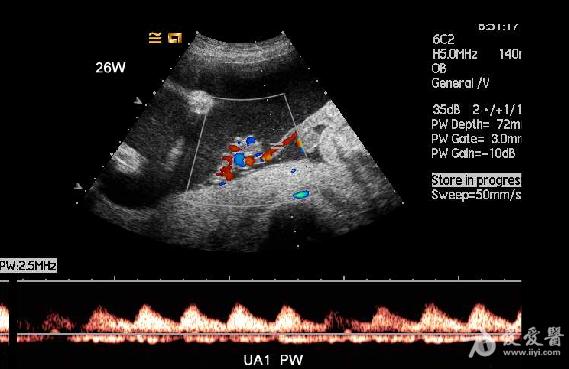

2.无心畸胎的脐带为单脐动脉,PW显示为入胎动脉血流,其血流频谱所显示的心率、心律与正常胎儿的心率、心律完全一致。但其脐动脉的阻力指数明显低于正常胎儿。说明异常胎儿的血供完全来自于正常胎儿心脏的“泵”。

6、频谱及彩色多普勒血流显像可显示无心畸胎脐动脉及脐静脉内血流方向与正常胎儿相反,无心畸胎脐动脉血流从胎盘流向胎儿髂内动脉达胎儿全身,脐静脉血流从胎儿脐部流向胎盘,正好与正常胎儿脐动脉、脐静脉血流方向相反。

1.无心畸胎序列征CDFI可显示胎体内有血液流动,其脐带内有血流信号。而死胎胎体及脐带内无血流显示。